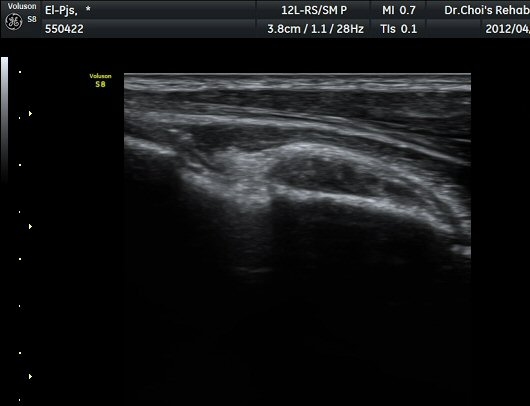

ÆÈ²ÞÄ¡ ¾ÕÂÊ È²µò¸é°Ë»ç¿¡¼­ Á¤»óÀûÀ¸·Î À̵ιڱ٠ÈûÁÙ°ú »ó¿Ïµ¿¸ÆÀÌ °üÂûµÈ´Ù(±×¸² 1).

ŽÃËÀÚ¸¦ ÆÈ²ÞÄ¡ ¸»´ÜÀ¸·Î À̵¿ÇÏ´Ï À̵ιڱ٠ÈûÁÙÀÇ ºñÈÄ¿Í ÈûÁÙ ÁÖÀ§¿¡ Àú¿¡ÄÚ ¼ö¾×Àú·ù°¡ ]

°üÂûµÈ´Ù(±×¸² 2, 3, 4, 5). ŽÃËÀÚ¸¦ ¸»´ÜÀ¸·Î À̵¿ÇÒ ¶§ ŽÃËÀÚ¸¦ ¸Ó¸®ÂÊÀ¸·Î °æ»ç(tilting)½ÃÄѾß

À̵ιڱ٠ÈûÁÙ¿¡ Á÷°¢ ÀÇ ÃÊÀ½ÆÄ Á¶»ç°¡ °¡´ÉÇÏ¿© À̵ιڱ٠ÈûÁÙÀÌ °í¿¡ÄÚ·Î °üÂûµÈ´Ù.